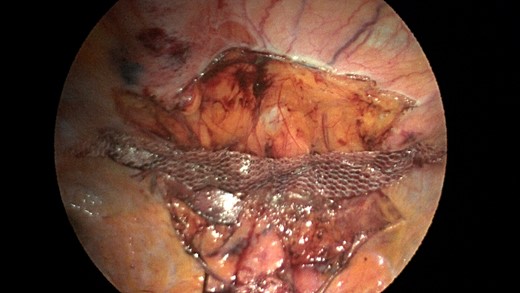

Patient underwent a laparoscopic approach in lithotomy positioning with the primary surgeon working between the legs. Three working ports were used, a 12 mm port at the umbilicus and two 5 mm ports; one in the LUQ and one in the RUQ. Upon initial laparoscopy multiple loops of small bowel were progressively reduced out of the hernia sac which also included the ascending colon and part of the transverse colon (Figs 3 and 4). All the small bowel and the colon appeared viable. The redundant parietal peritoneal hernia sac was excised out of the right inferior hemithorax utilizing a LigaSure (Covidien) (Fig. 5). The falciform ligament was also taken down all the way to the diaphragm. The defect in the diaphragm measured to be approximately 9 cm by 4 cm. A section of Pariatex composite mesh was then trimmed to 2 cm in width by 9 cm in length. Three stay sutures of 0 Ethibond were placed laterally and in the middle of the mesh. This was placed into the peritoneal cavity after soaking it in vancomycin with local anesthetic. The sutures were then percutaneously brought through the diaphragm edge that was unattached to the anterior abdominal wall and then subsequently through the anterior abdominal wall. These were then tied thereby re-approximating the unattached edge of the diaphragm to the anterior abdominal wall near the xiphoid (Fig. 6). Additional 0 Ethibond sutures were placed in between these initial ones percutaneously with a suture passer.

Laparoscopic view of the retroxyphoid defect in the diaphragm demonstrating multiple loops of small bowel and colon.

Closer view of the retroxyphoid defect demonstrating its large size with the edge of the diaphragm unattached to the undersurface of the abdominal wall.

A sleeve of Parietex composite mesh cut to act as a suture bolster under the diaphragm edge to prevent the sutures from pulling through the diaphragm muscle.